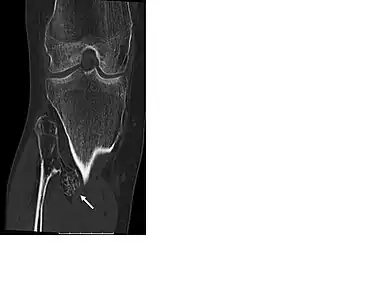

multiple osteochondromas around the knee